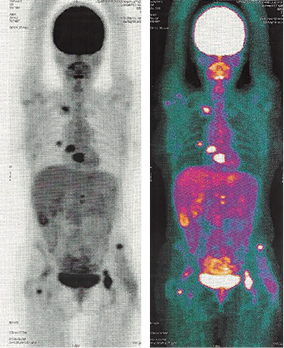

A los 12 meses de control por oncología, manifestó sensación de fatiga a los 30 minutos de ejercicio, así como presencia de tos predominantemente nocturna, por lo que se solicitó TAC de tórax, que fue reportada como normal, así como resonancia magnética de la zona quirúrgica; no se encontraron recidivas. En el control a los 17 meses postdiagnóstico, se encontró una baja de peso de cuatro kilogramos en un mes, por lo que se efectuó una tomografía por emisión de positrones (PET)/CT de cuerpo completo, la cual reportó la presencia de lesiones líticas en esqueleto axial y apendicular siguientes: extremo medial de clavícula derecha, apófisis transversa derecha de T8, hemicuerpo izquierdo de T9, apófisis transversa izquierda de L1, espina iliaca anterosuperior izquierda, acetábulo derecho, acetábulo izquierdo, isquion izquierdo, cuello quirúrgico de fémur derecho, además de nódulos pulmonares bilaterales (Figuras 3 y 4). Se catalogó en ese momento en estadio IVB. Actualmente es manejada de manera paliativa con ciclos de dacarbacina, gemcitabina, denosumab y factor estimulante de colonias de granulocitos, además de recibir radioterapia 30 Gy en 10 sesiones. Se encuentra (10-I-2015) en protocolo para realizar vertebroplastia o cifoplastia con metilmetacrilato con relación a manejo de dolor óseo; se anota que continúa realizando 30 minutos de ejercicio aeróbico diario.

Figura 3: Estudio PET/CT mostrando lesiones en esqueleto axial y apendicular con características líticas.